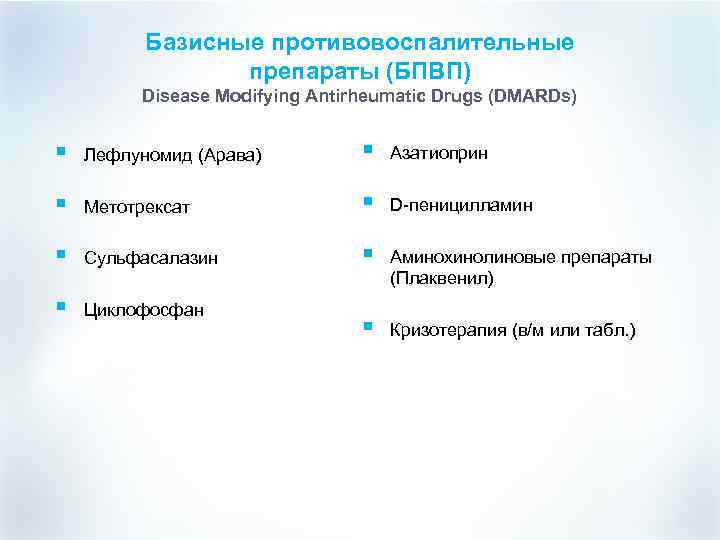

Базисные противовоспалительные препараты (БПВП) Disease Modifying Antirheumatic Drugs (DMARDs) § Лефлуномид (Арава) § Азатиоприн § Метотрексат § D-пеницилламин § Сульфасалазин § Аминохинолиновые препараты (Плаквенил) § Циклофосфан § Кризотерапия (в/м или табл. )

Базисные противовоспалительные препараты (БПВП) Disease Modifying Antirheumatic Drugs (DMARDs) § Лефлуномид (Арава) § Азатиоприн § Метотрексат § D-пеницилламин § Сульфасалазин § Аминохинолиновые препараты (Плаквенил) § Циклофосфан § Кризотерапия (в/м или табл. )